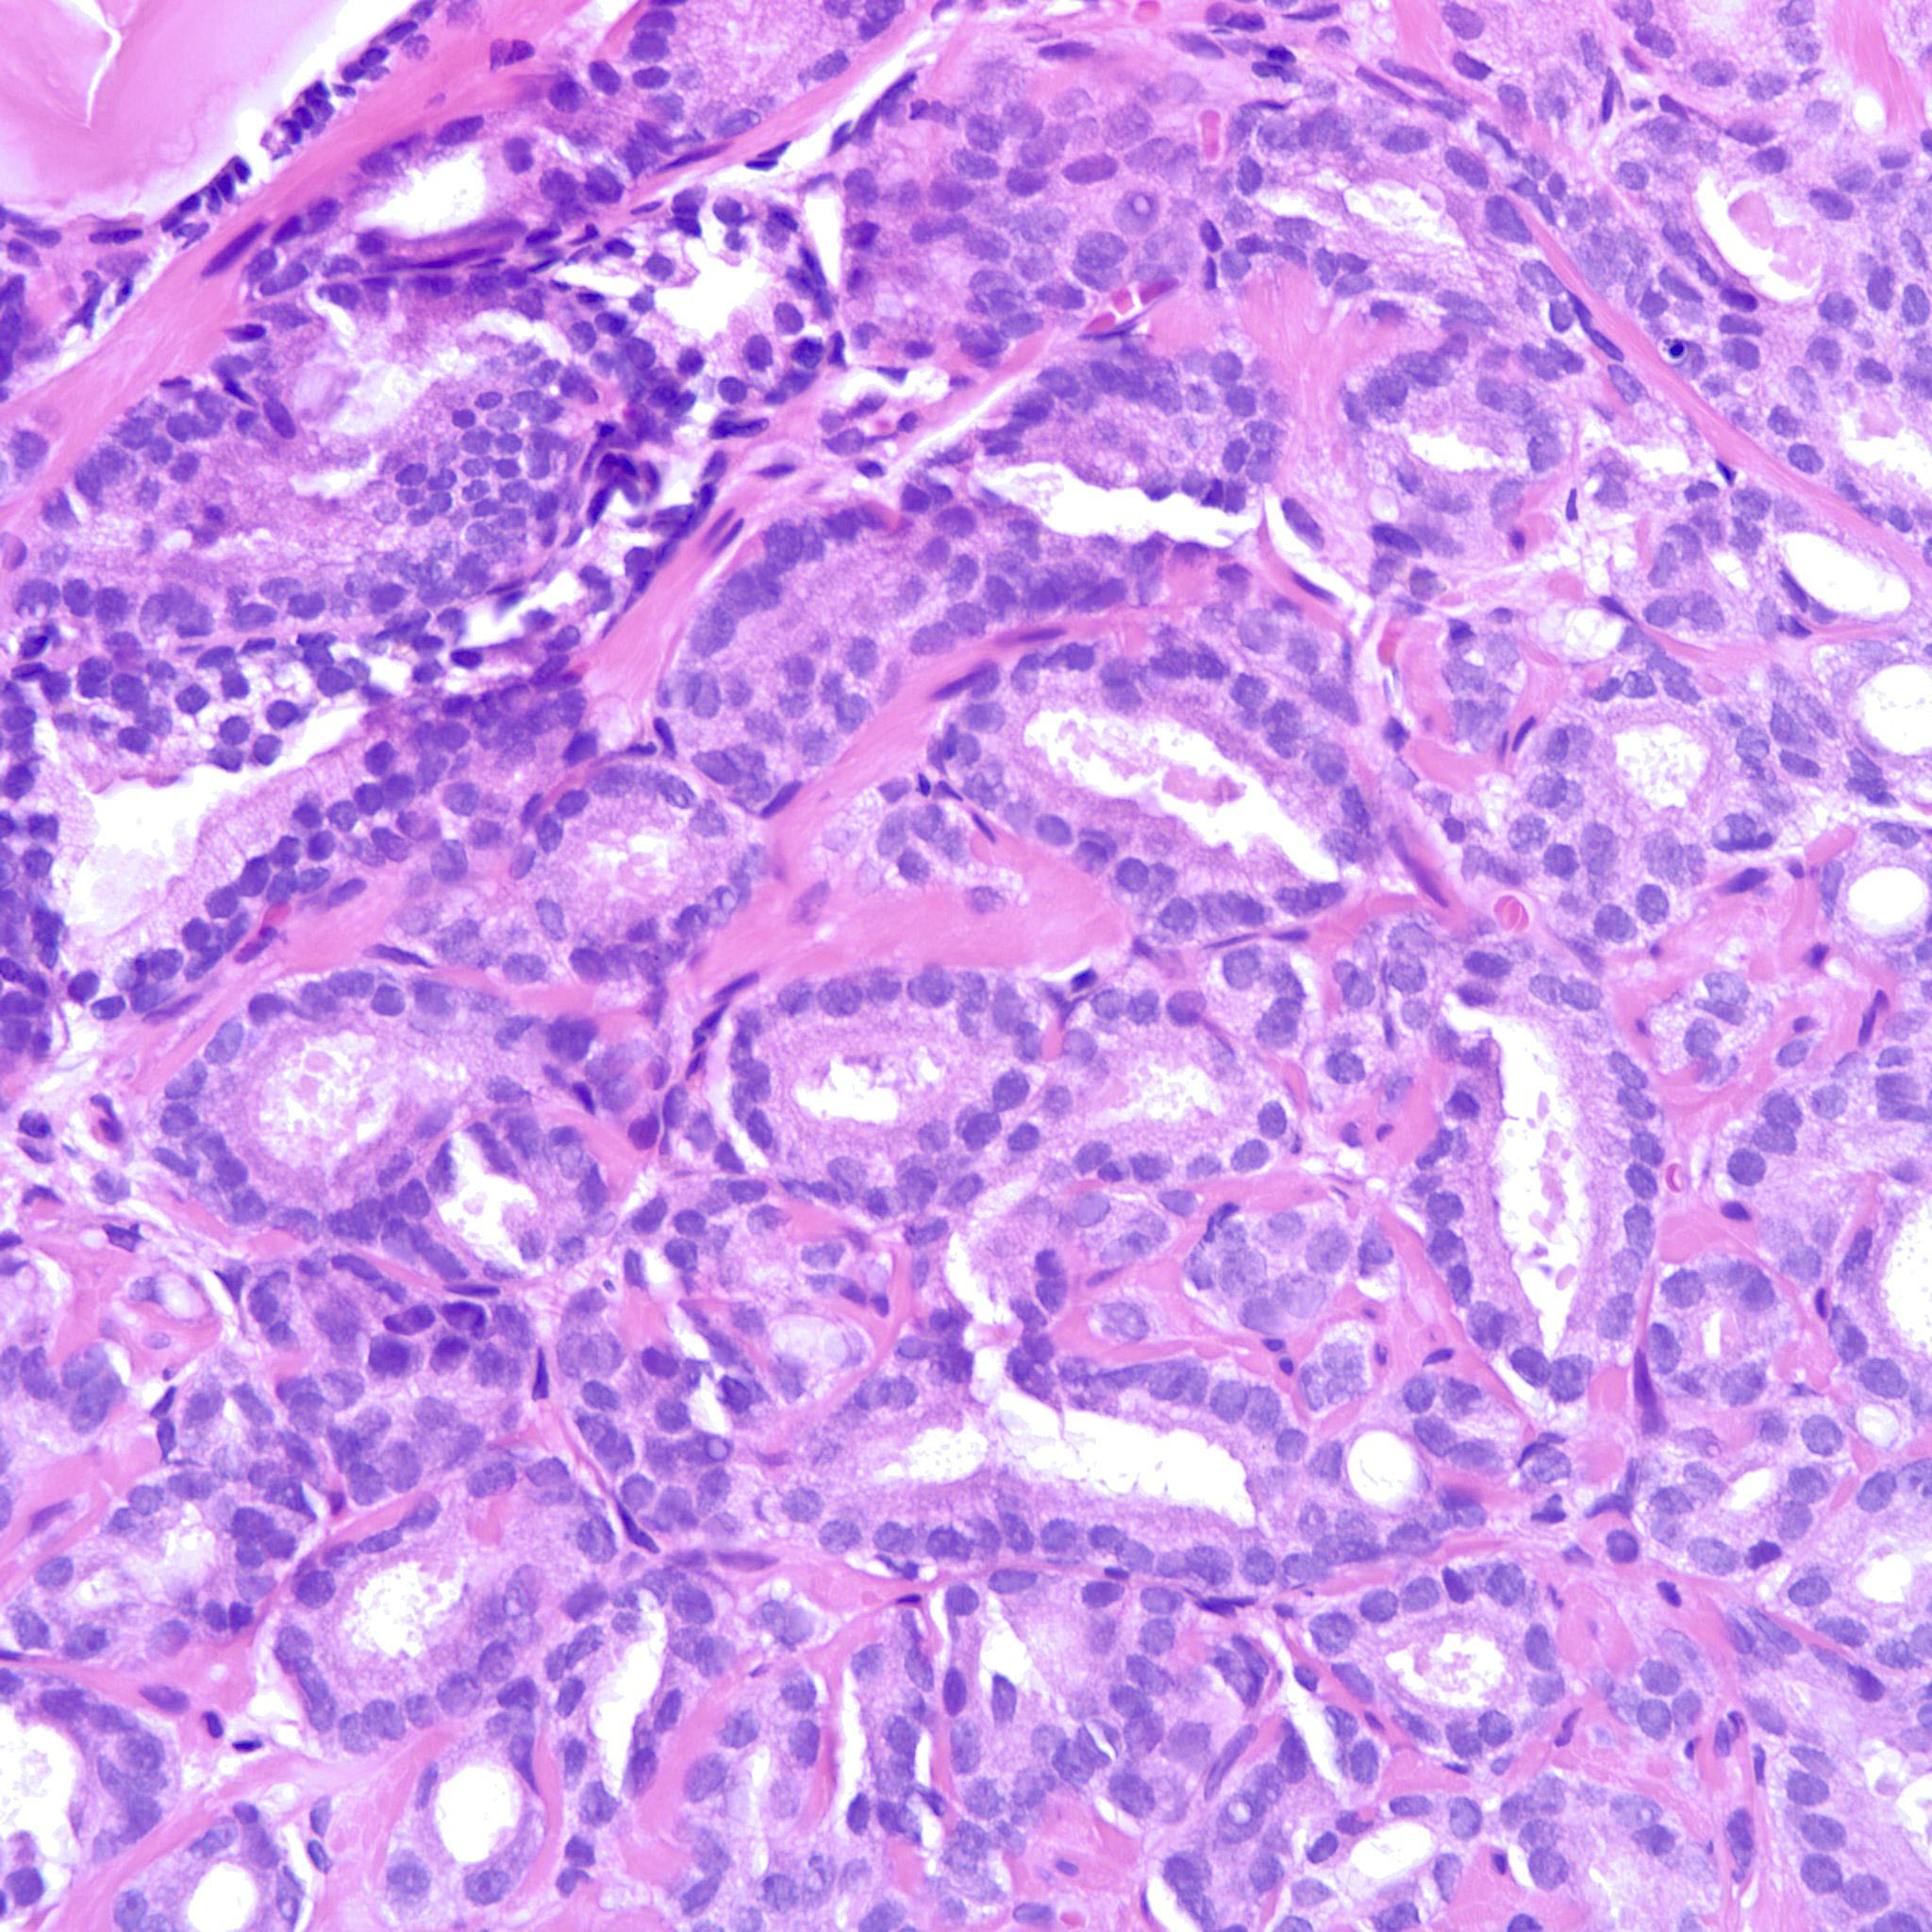

Prostate cancer grading

Case ID: 214